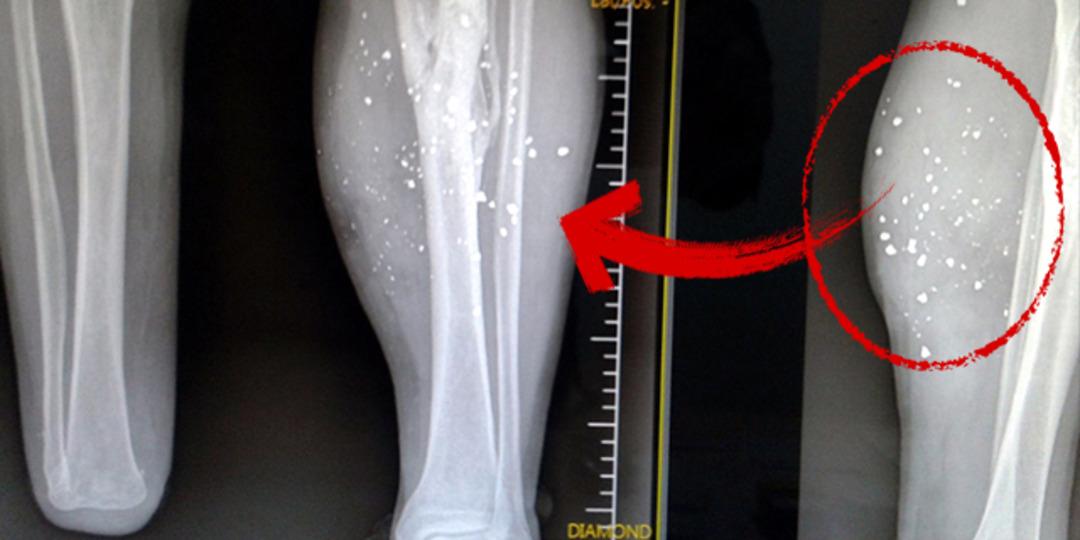

Yıldız, çatışmadan sonra sol bacağında şarapnel parçaları kaldığını, 20 yıl sonra MR çektirdiğinde vücudunda omuriliğine yakın bir şarapnel parçası daha görüldüğünü söyledi.

Doktorların riskli olduğu için şarapnel parçalarını almadığını ifade eden Yıldız, şunları aktardı: "Sol bacağımda oldukça yoğun şarapnel parçaları var. Şarapnel parçalarından dolayı bacağımı kaybetme durumu yaşadım. Ayağım iltihap yaptı. Çok uzun süren tedavi sonrasında sol ayağım düzeltildi. Yirmi yıl sonra MR'a girdiğimde omuriliğime yakın şarapnel parçası tespit edildi. Ben buradan GATA'ya gittim. 'Alamayız, çok riskli bölge' dediler. Şu an vücudumda şarapnel parçalarıyla yaşıyorum. Ben şunu söylüyorum; vatanımızın ha kuru ekmeğini yemişiz, ha bir kör kurşununu veya bir el bombasını... Bu vatan bize annelik yapıyor. Vatanımız, bayrağımız için ayağımız değil, gerekirse canımız da gidecek ama ay yıldızlı bayrağımız ebediyen dalgalanacak."